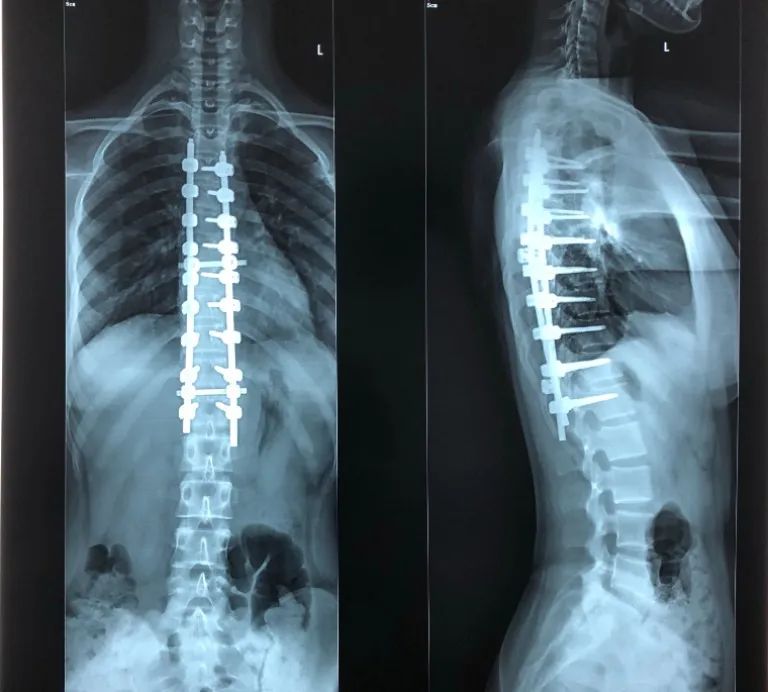

一般可以通过X线检查,且清晰看到各个相互连续的生理弯曲,能够增加脊柱的弹性,进而减轻和缓冲震荡,防止外力对脊髓和大脑造成损伤。